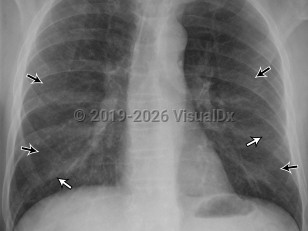

Acute respiratory distress syndromeAcute respiratory distress syndrome

Pulmonary edema

Acute eosinophilic pneumoniaAcute eosinophilic pneumonia